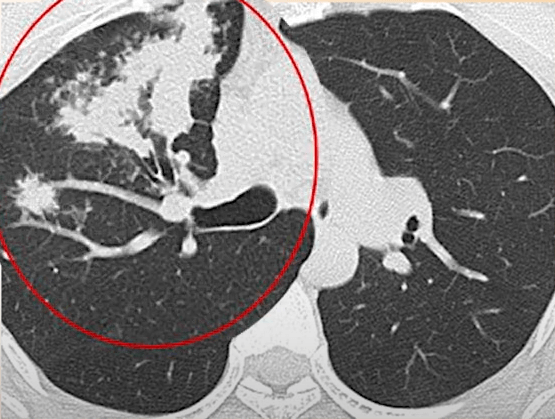

[흉부 CT]

흉부 X-ray촬영 검사로 정확한 결핵의 진단이 어려운 경우 휴부 단층촬영을 시행하고 의사의 판독으로 진단한다.